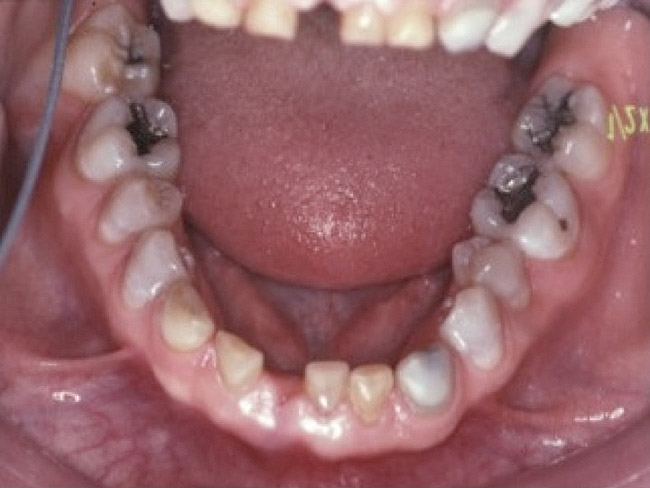

Figure 7. The mandibular incisors are loose, and No. 25 has recently been lost.

Figure 7

Loss of vertical dimension can be assessed through patient examination intraorally, extraorally, and functionally. Missing teeth and/or teeth worn from clenching or bruxing are the most common intraoral signs of a decreased VDO. Congenitally missing teeth can result in loss of vertical dimension with possible implications of compromised comfort, speech, and chewing (Figure 6 through Figure 8).